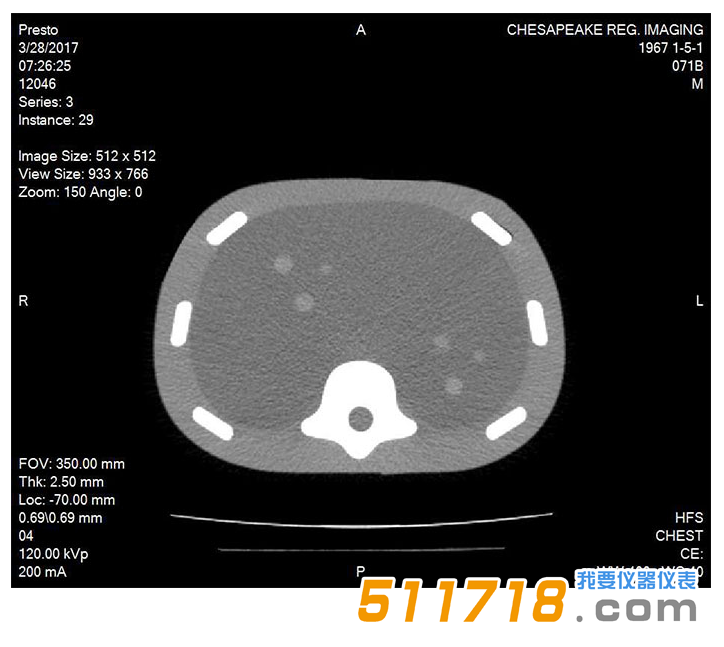

071B CT圖像